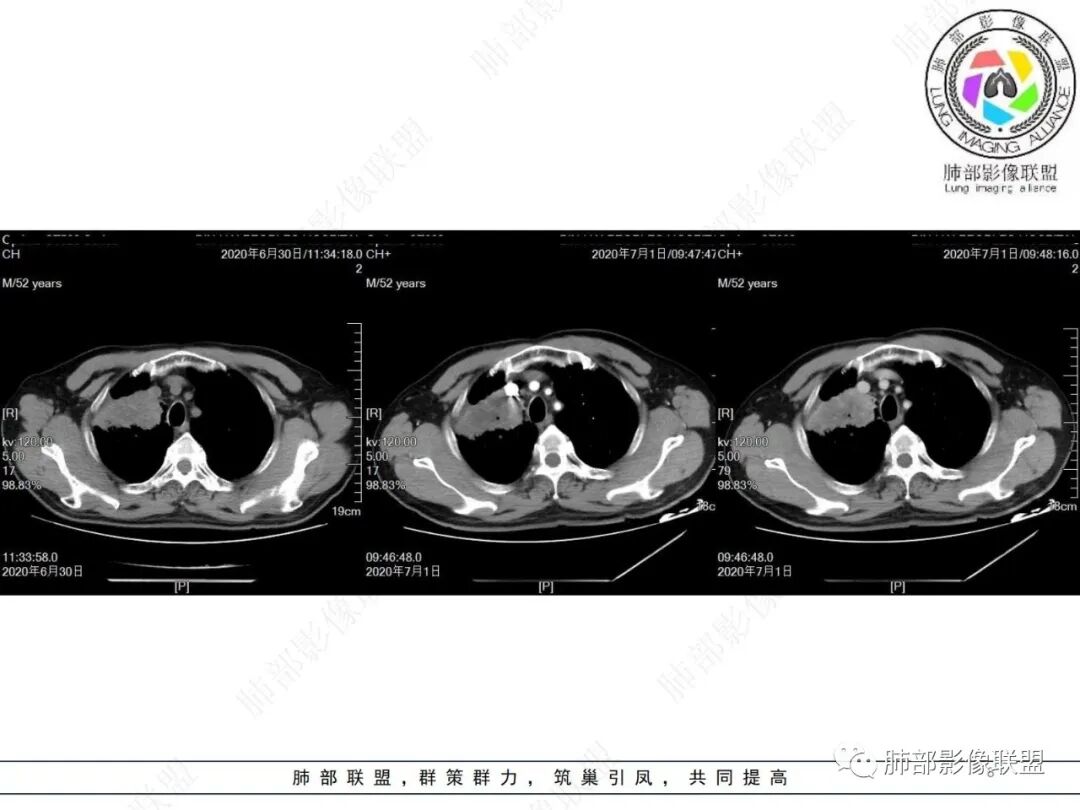

中年男性,有长期吸烟史,右肺上叶不规则肿块,边缘膨隆有分叶,支气管截断,不均匀强化,内有多灶性坏死,癌胚抗原升高,考虑肺癌可能性大,鳞癌可能。鉴别腺癌。

中年男性,吸烟病史,右肺前叶块状占位性病变伴前段支气管截断,病变周围可见结节及斑片状影,增强肿块不均匀性强化,纵隔淋巴结肿大,结合实验室检查,首先考虑肺小细癌,鉴别鳞癌、大细胞。

右肺上叶不规则形软组织密度肿块影,边缘见分叶,毛刺,病灶呈宽基底与胸膜相连,病灶内见坏死,增强扫描呈不均匀性强化,右肺上叶支气管截断,纵隔内见肿大淋巴结,肿瘤标志物增高,考虑鳞癌可能,鉴别小细胞癌,腺癌。

老年人,右肺上叶肺不张伴阻塞性炎症,右肺上叶支气管闭塞,增强病灶强化不均匀,可见边缘不清晰的坏死,纵膈淋巴结增大,考虑中央型肺癌,鳞癌可能性大。

右肺上叶不规则肿块,分叶、毛刺,上叶支气管截断,断端圆钝,不均匀强化,其内空泡及坏死,坏死边界不清,考虑腺癌或腺鳞癌,鉴别鳞癌

右肺上叶团块影,边缘膨隆,支气管近端截断,肿块内密度不均匀,见片状坏死,边界不清,纵隔肿大淋巴结,CEA明显增高,考虑恶性,鳞癌?腺鳞癌?

中年男性,长期吸烟,CT示右肺上叶肿块影,有分叶,毛刺,胸膜牵拉,支气管截断,边缘斑片影,病变内有坏死,强化,淋巴结肿大,首先考虑鳞癌可能性大,鉴别腺鳞癌

右肺上叶占位,支气管阻塞截断,病变周围可见结节及斑片状影,密度不均,坏死边缘不清,纵隔淋巴结肿大,中年男子,吸烟史,考虑鳞癌、腺鳞癌,鉴别结核

沼泽样坏死,支气管截断,周围阻塞性炎症,并淋巴道水肿,考虑腺鳞癌,鳞癌

右上叶支气管截断呈斜坡状,不均匀强化,低密度区实质区边界不清,老年男性,长期吸烟史,考虑恶性,鳞癌首选

长期抽烟的老头,右肺上叶不规则肿块,边缘膨隆有分叶,支气管截断,不均匀强化,内有片状坏死,考虑肺癌,常规思路鳞癌可能。鉴别腺癌。

中年男性,长期吸烟,右肺上叶不规则肿块,边缘膨隆有分叶,支气管截断,不均匀强化,内有多灶性坏死,癌胚抗原升高,考虑肺癌